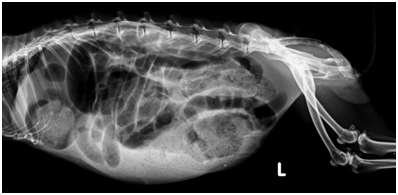

Op deze foto is duidelijk te zien dat er grote slangvormige structuren in de buik zitten die bijna de hele buik in beslag nemen. Dit zijn de darmen die vol zitten met gas. Een konijn eet vaak ruwvoer en dit heeft een korrelig aspect op een radiografie. Dit kunt u goed zien in de witte zone onderin de buik. Normaal moet er meer voedsel dan gas in een konijnenbuik te zien zijn, hier is dat andersom. Een foto is belangrijk omdat er meer oorzaken zijn van een konijn dat slecht eet en een dikke buik heeft, zoals baarmoederontsteking.